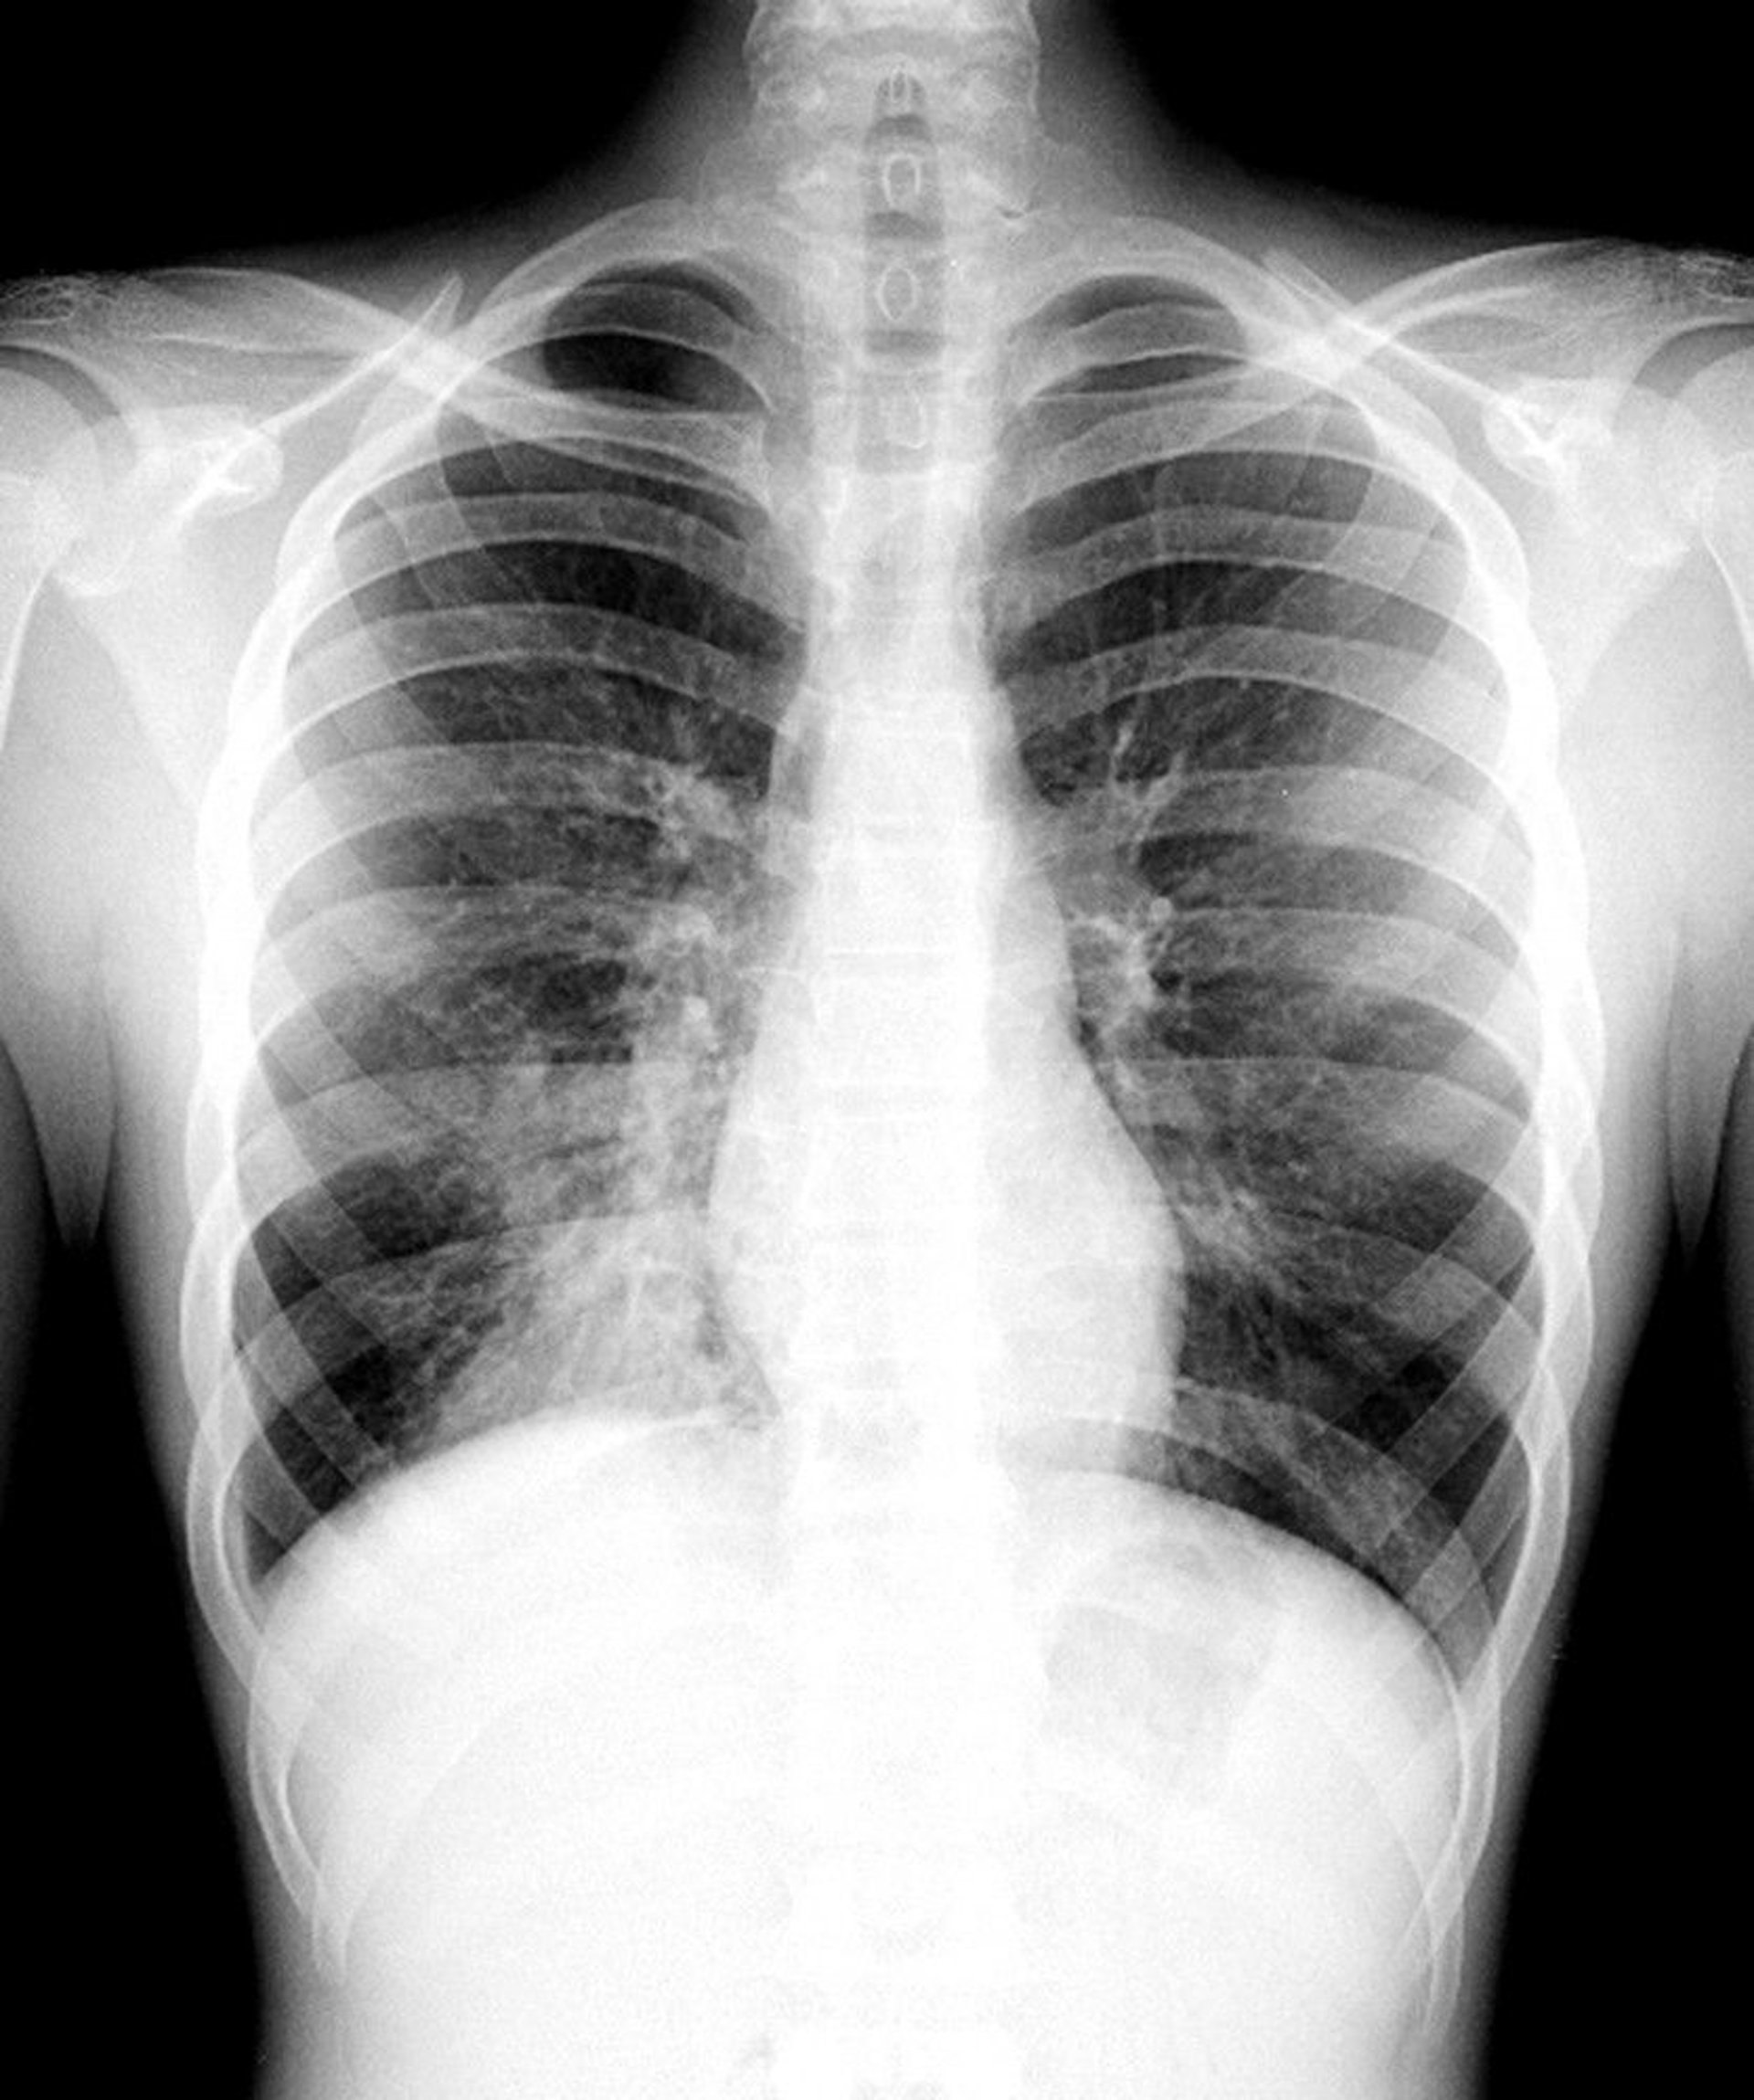

Pneumonia of the Right Lower Lobe

This chest x-ray shows an infiltrate that does not obscure the right heart border (ie, there is no silhouette sign). Because the silhouette sign develops when 2 contiguous structures have a similar radiodensity, the part of the lung affected by this infiltrate is the part not contiguous with the right heart border; that part is the right lower lobe.